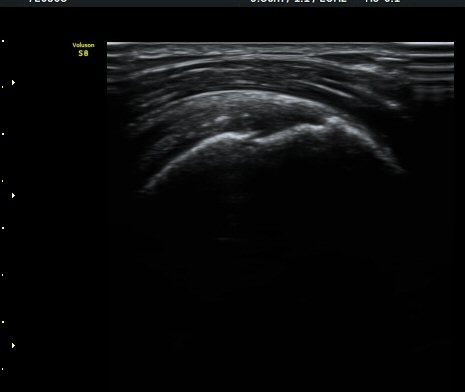

¼ö¾×Àú·ù°¡ °üÂûµÈ´Ù(±×¸² 1, 2). °ß°©ÇÏ±Ù°Ç Á¾´Ü¸é°Ë»ç¿¡¼­ °ß°©ÇϱٰÇÀÇ °üÀý³»ºÎÀ§(±×¸² 3)

¿Í ¼Ò°áÀý »óºÎ(±×¸² 4)¿¡¼­ ƯÀÌ ¼Ò°ßÀ» º¸ÀÌÁö ¾Ê´Â´Ù.